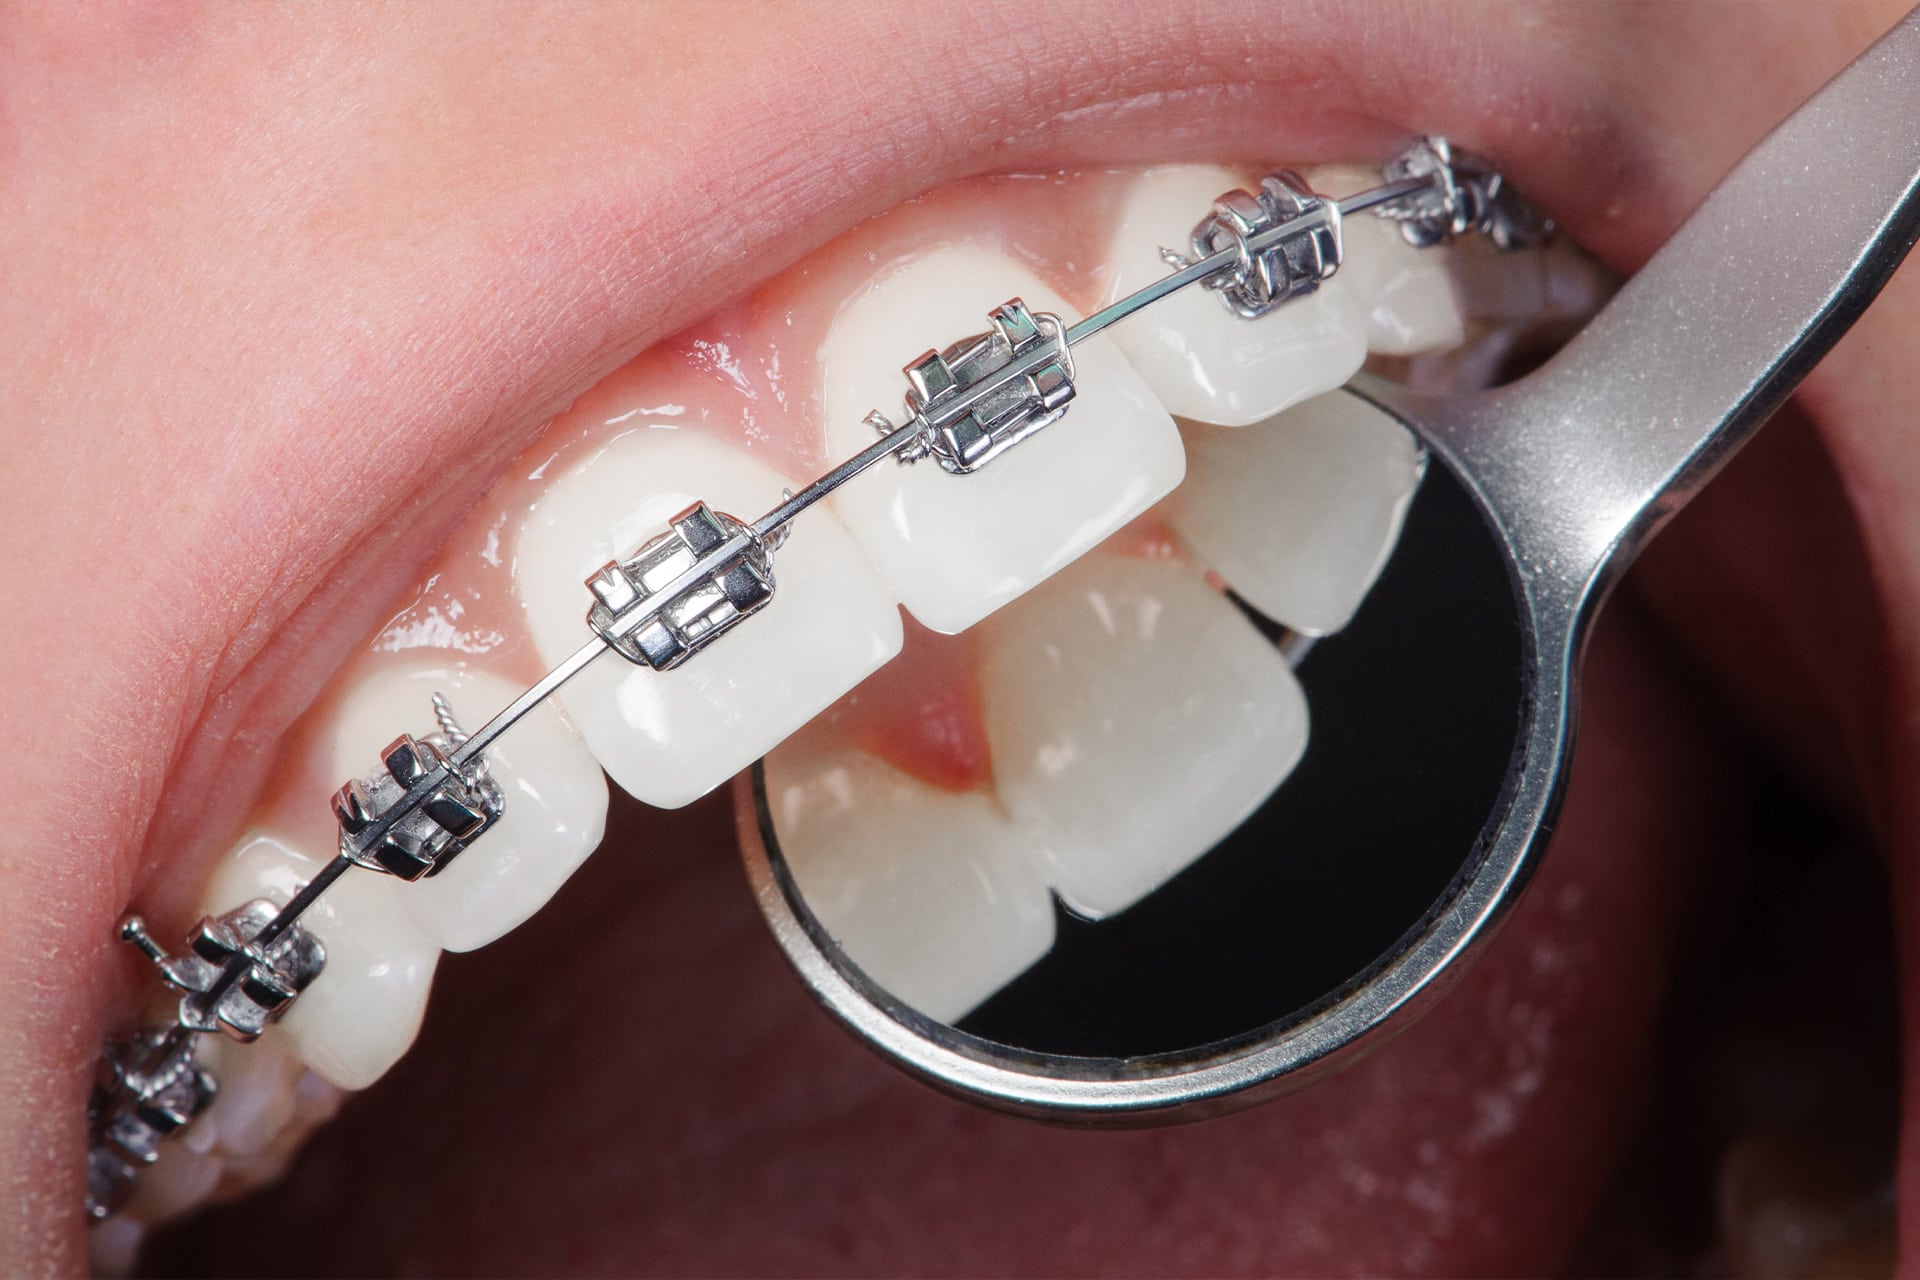

La ortodoncia es la especialidad de la odontología que se encarga de corregir las malposiciones de los dientes y las alteraciones de la mordida. Si tienes los dientes torcidos, apiñados o una mordida abierta o cruzada, la ortodoncia puede ayudarte a lograr una sonrisa más estética y funcional.

Son los aparatos más tradicionales. Pueden ser metálicos, de cerámica o zafiro, y se adhieren a los dientes para aplicar fuerza y moverlos gradualmente.